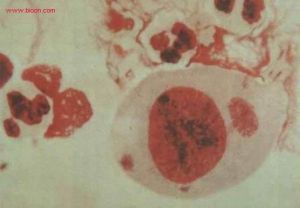

包涵體是病毒在增殖的過程中,常使寄主細胞內形成一種蛋白質性質的病變結構,在光學顯微鏡下可見。多為圓形、卵圓形或不定形。一般是由完整的病毒顆粒或尚未裝配的病毒亞基聚集而成;少數則是宿主細胞對病毒感染的反應產物,不含病毒粒子。

包涵體有的位於細胞質中(如天花病毒包涵體),有的位於細胞核中(如皰疹病毒),或細胞質、細胞核中都有(如麻疹病毒)。